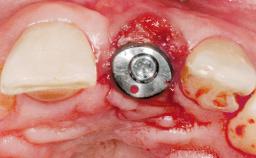

Early Placement of an Implant in a Maxillary Right Central Incisor Site

This 41-year-old female patient was referred to the clinic for the replacement of the right central incisor, since the tooth had developed a root fracture in the long axis that made extraction necessary. The healthy, non-smoking patient was first seen with the tooth still in place. A detailed Esthetic Risk Assessment was performed.The patient was worried about her dental esthetics and had high expectations for a successful treatment outcome from an esthetic point of view. The patient had a medium lip line that displayed parts of the gingiva in the anterior maxilla upon smile.